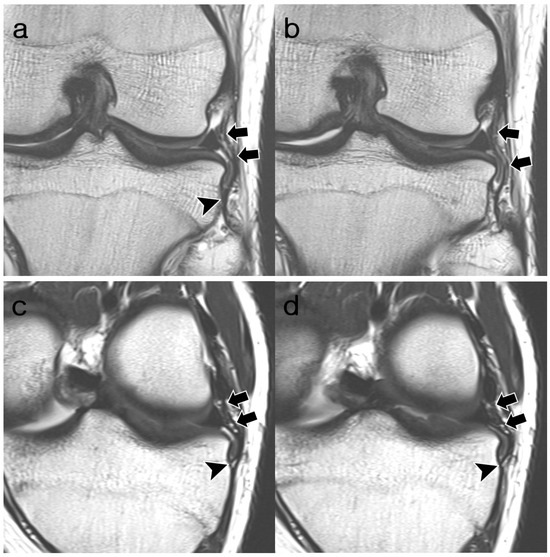

3.2. ALL Visibility

3.3. ALL Morphology